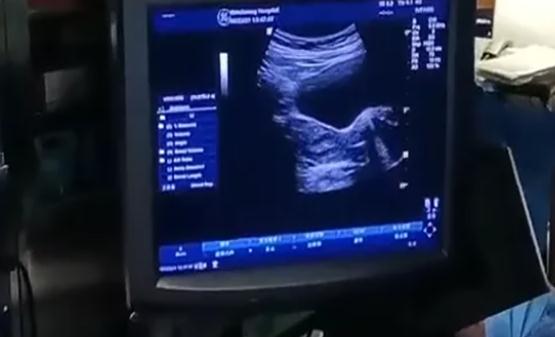

胚胎移植是试管婴儿一个非常重要的环节,主要是通过体外受精获取胚胎的方式,通过超声的引导下将胚胎移植到女性子宫腔内来达到怀孕的目的。胚胎移植是经腹部B超的引导下进行的,实验室的工作人员会将含有胚胎的培养液抽到胚胎移植管中,转交给临床医生,临床医生会在腹部超声的引导下,将胚胎用移植管移植到女方的子宫腔内。这一过程就叫做胚胎移植。